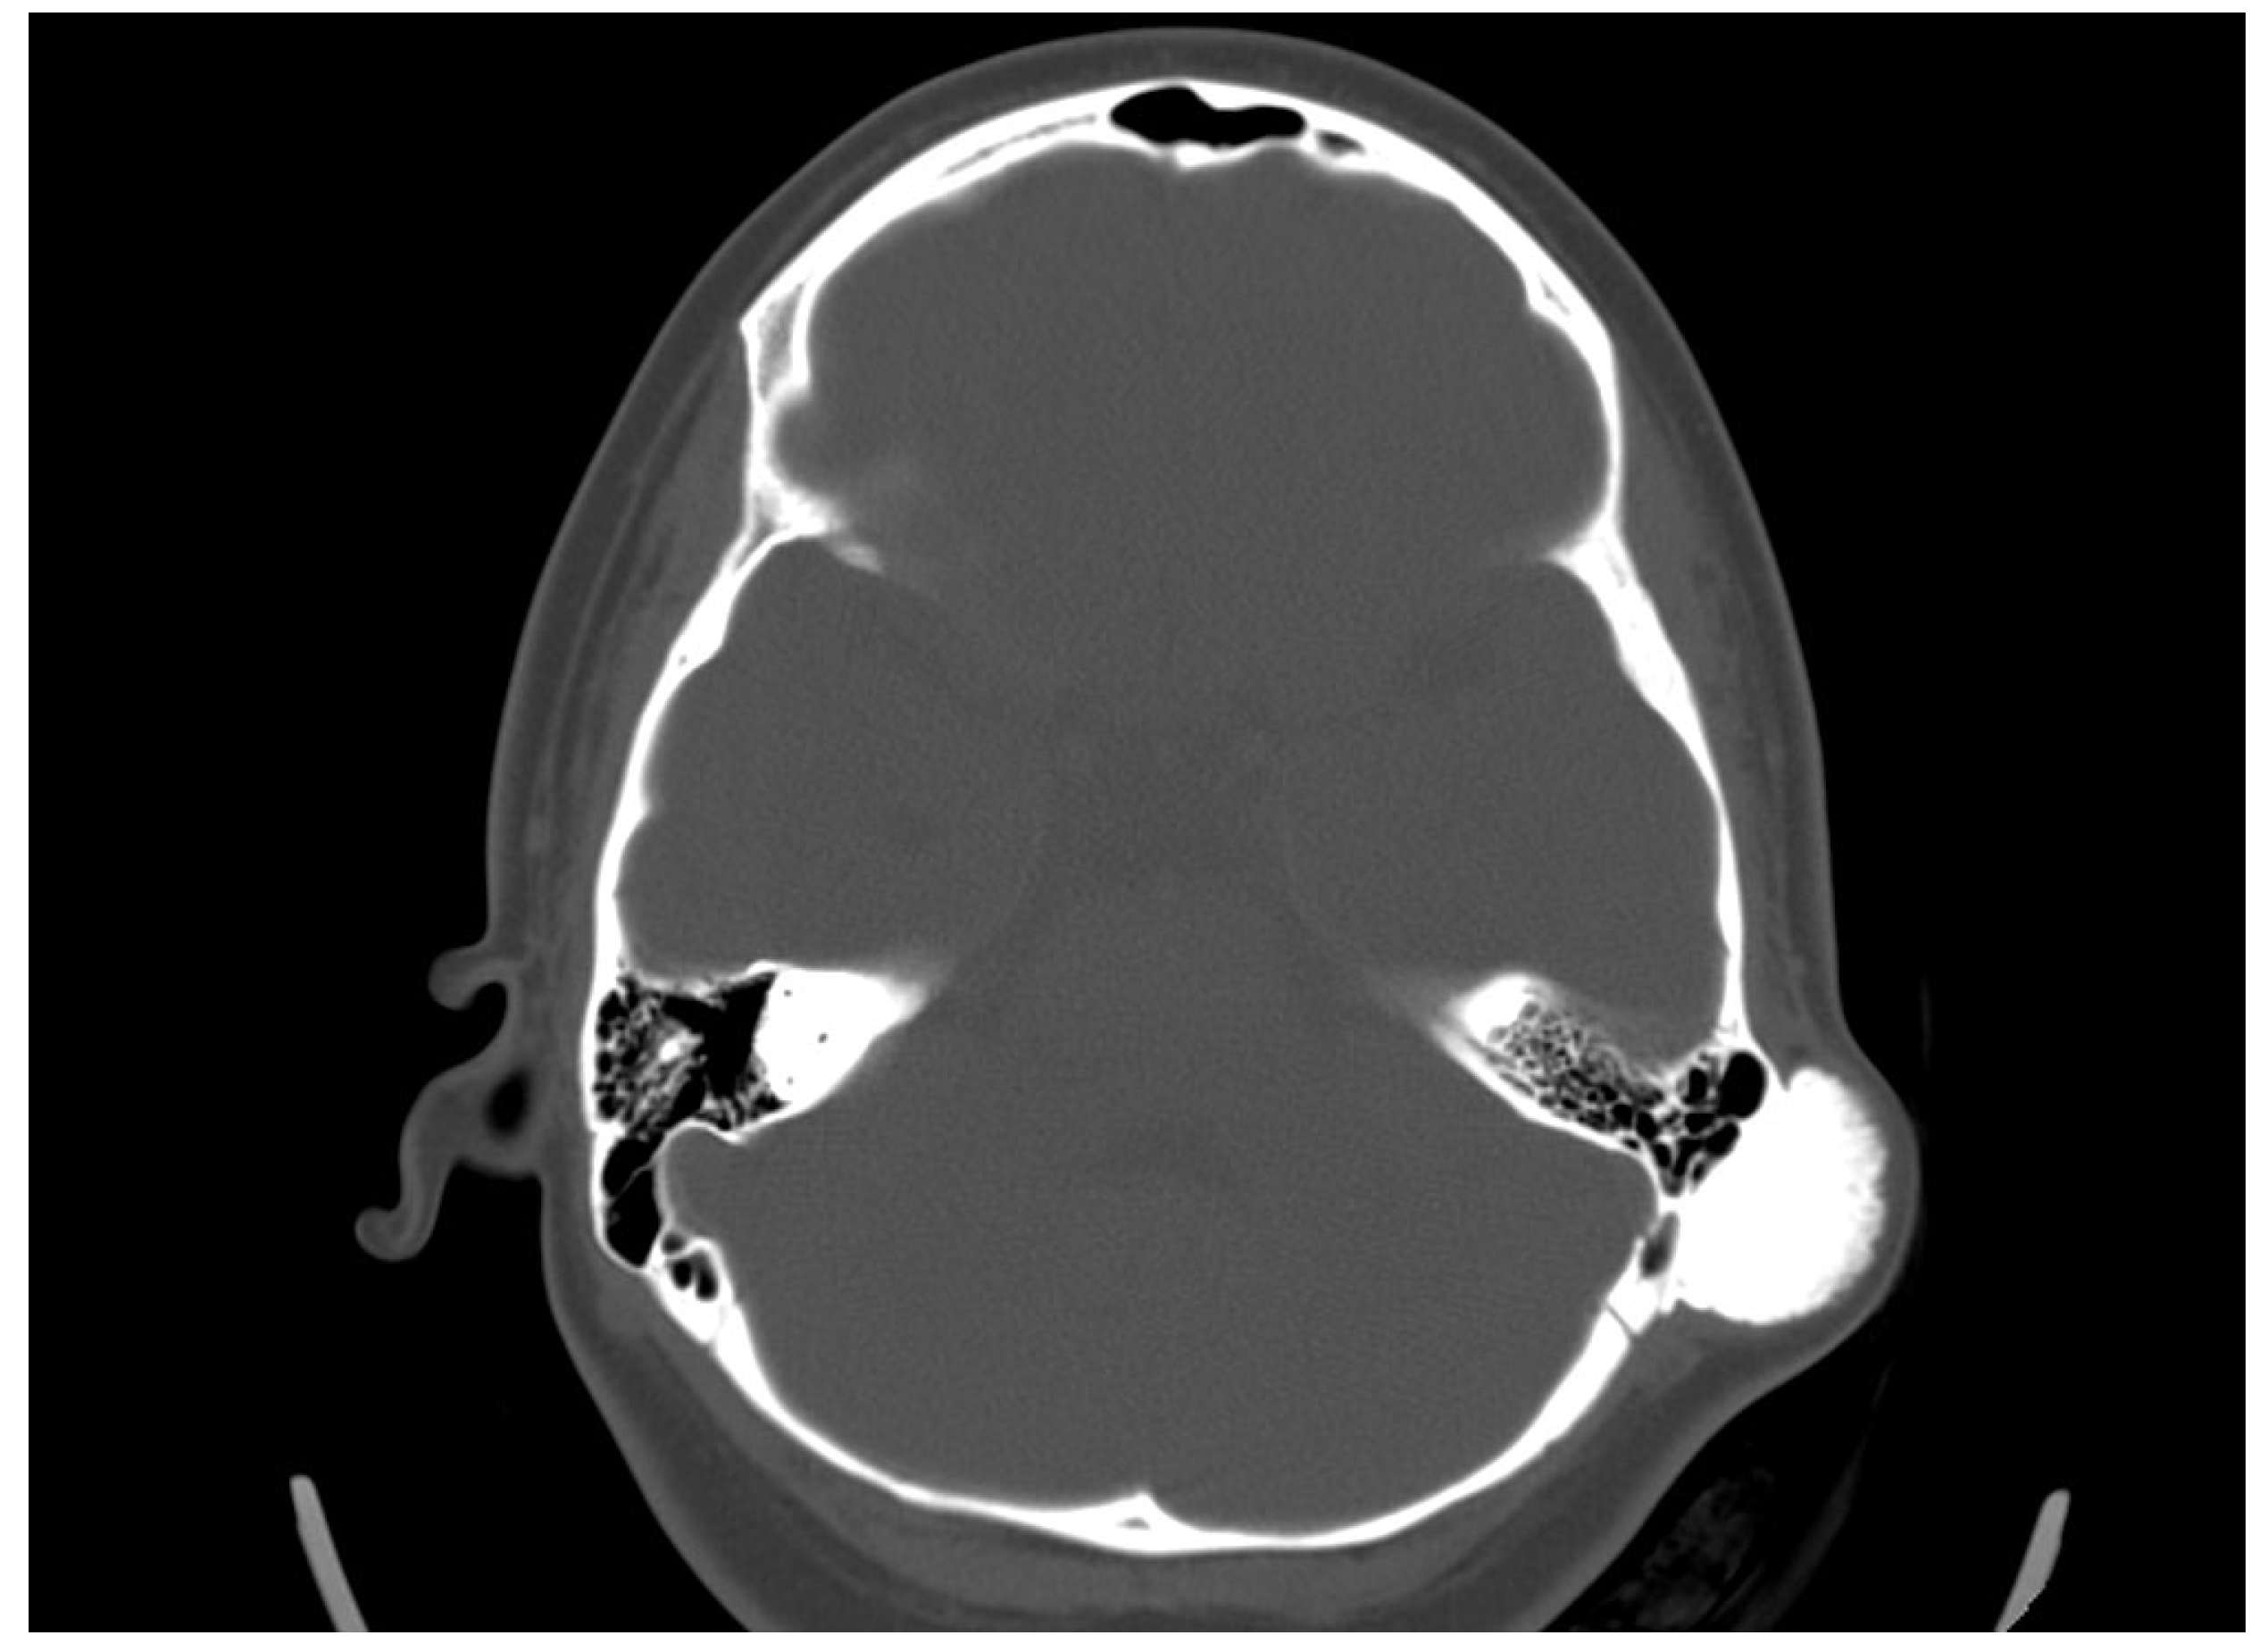

She was admitted to the ENT department, and an otorhinolaryngological examination was performed. In the retroauricular area, tumor formation was palpated, and the overlying skin was mobile with no retraction. Otoscopy did not detect any abnormalities in the external auditory canal and the tympanic membrane. The audiological examination did not indicate any hearing loss. A computed tomography scan was conducted. In the axial plane, a bone tumor formation with a diameter of 19/31 mm in the mastoid process was detected. There was a passive dislocation of the soft tissues with no invasion (Figure 3).

Figure 3.

Axial CT scan revealing an osteoma in the cortex of the mastoid process, with no involvement of the surrounding cellular structures.